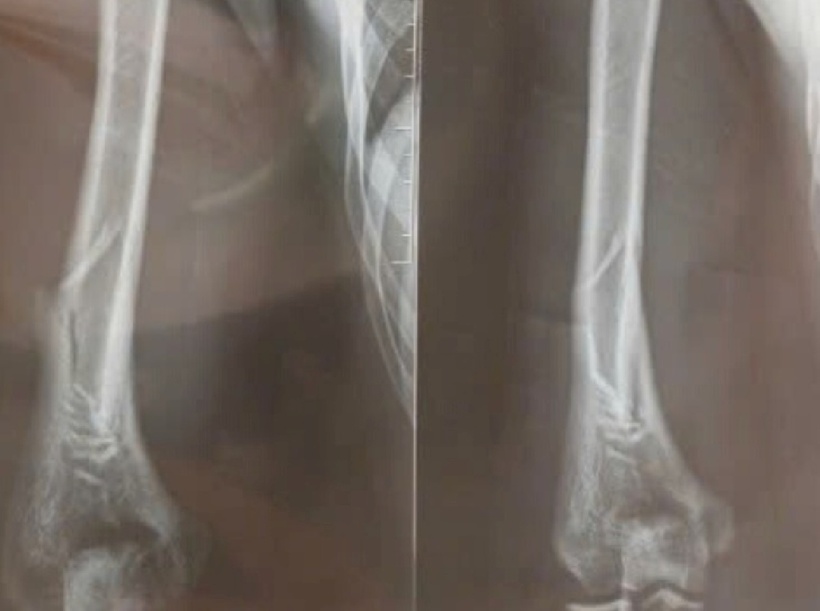

Ngay sau đó gia đình lập tức đưa bệnh nhân vào Khoa Cấp cứu, Bệnh viện Đa khoa Hà Đông. Tại đây, sau khi được sơ cứu bằng cách cố định tạm thời bằng nẹp gỗ, D. được chụp X-quang và xác định bị gãy ở vị trí 1/3 dưới xương cánh tay phải. Bệnh nhân được chỉ định phẫu thuật kết hợp xương bằng nẹp vít khóa.

Ảnh chụp X-quang cánh tay phải của bệnh nhân. Ảnh: Báo Tuổi trẻ.